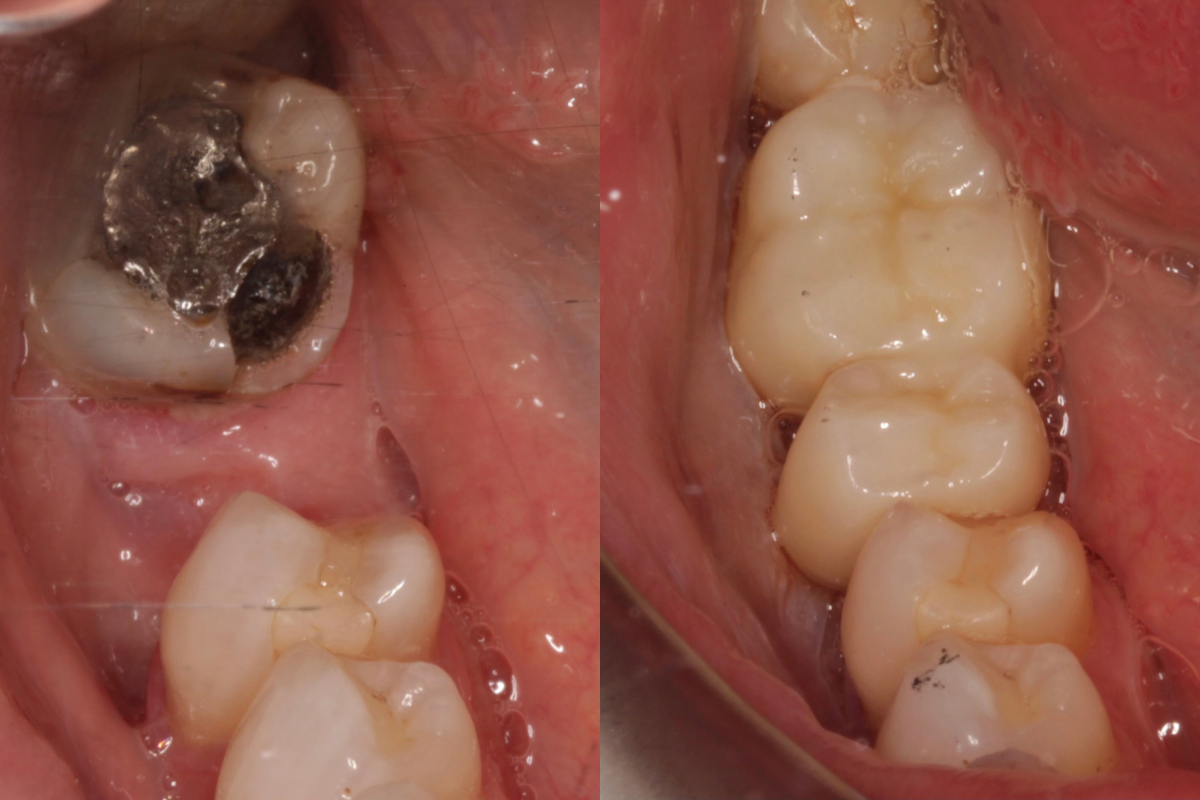

Before

After

Highlights: advanced digital planning using the latest CBCT scan technology, implant placement with pinpoint precision using a printed surgical guide, high-aesthetic and high-strength premium zirconia crown for a beautiful, natural, long-lasting result.